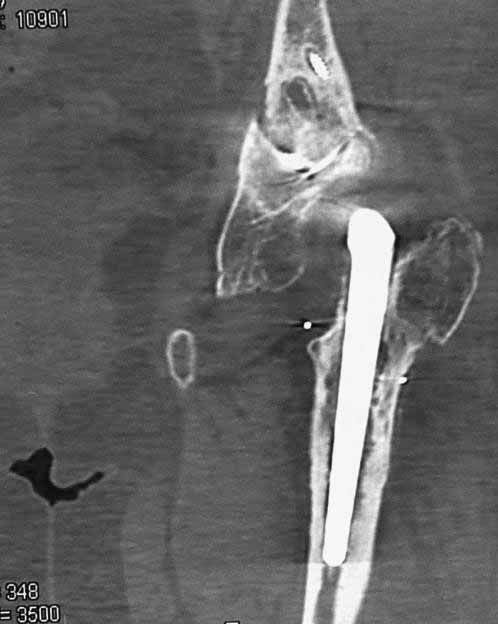

Уважаемые коллеги. Хотелось бы услышать мнения и советы по представляемому случаю. Пациентка 45 лет. Бесцементное эндопротезирование левого тазобедренного сустава 6 лет назад (впадина RM, Mathys, металл-металл, ножка Зульцеровская). За 10 лет до протезирования – коррегирующая остеотомия бедренной кости, которая не срослась в течение года до удаления пластины, а затем срослась в течение 3 месяцев иммобилизации в кокситной повязке. После протезирования получилось наблюдать пациентку почти постоянно, поскольку через 2 года синтезировал ей лодыжки на оперированной стороне, затем, через несколько месяцев удалил фиксаторы, а в 2009г. резецировал мениск на противоположной стороне. Боли все эти годы не беспокоили. Пациентка чуть выше среднего роста, вес тела нормальный. Физические нагрузки переносила хорошо. Работает на 7 этаже без лифта. Год назад экстирпация матки по поводу лейомиомы больших размеров. Несколько месяцев назад появились боли в области левого тазобедренного сустава. При рентгеновском и КТ исследованиях (июль с.г.) – нестабильность тазового компонента. От предложенной замены протеза пациентка на тот момент, слава богу, отказалась. Через какое то время боли в области левого тазобедренного сустава практически полностью прошли, а около 2 месяцев назад появилось ощущение патологической подвижности таза и боли в паху справа, которые через некоторое время уменьшились, а потом снова усилились после значительных физических нагрузок (много ходила по песку на пляже, носила тяжести). Ежедневно принимала диклофенак. На рентгенограммах – переломы правой лонной кости. Сейчас госпитализирована из-за болей в паху справа. Боли слева не беспокоят. На фоне снижения нагрузок в стационаре боли значимо уменьшились. Способна ходить без средств дополнительной опоры.В анализах крови чуть повышены трансаминазы и гамма-ГТ, моча без особенностей.

Вопросы: -правильно ли я расцениваю переломы как стрессовые на фоне неполноценного таза (pelvic insufficiency stress fractures)? -Можно ли так же расценить ситуацию на стороне протеза и, соответственно, не торопиться с ревизией, рассчитывая на вторичную стабилизацию? Уж больно не хочется менять ножку. -Если думать о ревизии, то когда? На представленных снимках тазобедренный сустав до и сразу после операции, затем 2 снимка 2009г., когда ничего не беспокоило, затем КТ 2-х месячной давности и вчерашние рентгенограммы обоих тазобедренных суставов.

Уважаемый Сергей,

Похоже Вы правы,это напоминает перегрузочный перелом, но вопрос о его причине остается открытым, просто ли это избыточная нагрузка на правую половину таза вследствие нестабильности чашки слева и ограничение нагрузки на левую половину, либо это гормональные изменения, приведшие к изменению метаболизма и перелому. Я бы дождался консолидации и поставил вопрос о замене чашки. Молодая женщина, 45 лет, пока еще можно обойтись достаточно простой манипуляцией, если процесс начался, его не остановить, но дальше будет намного сложнее.